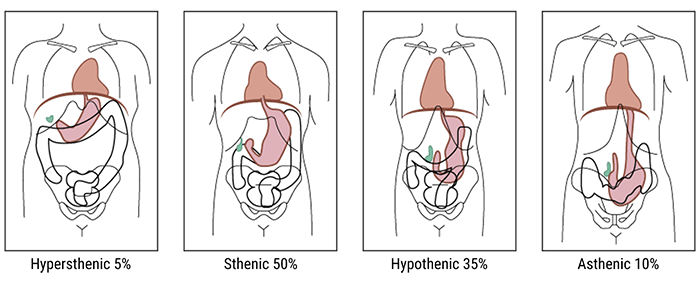

- Hypersthenic 5% of adults

- Sthenic 50% of adults

- Hyposthenic 35% of adults

- Asthenic 10% of adults

Hypersthenic

The first body type to discuss is the “hypersthenic” one.

A hypersthenic person is a very muscular, thick-set individual, with a broad bony chest and high diaphragm. In this body type, the stomach tends to lie transversely and the gall-bladder horizontally high in the abdomen, well away from the midline. The transverse colon is also high, as well as the heart and the lungs.

Sthenic

A sthenic person is a muscular, thick-set individual similar to hypersthenic but not quite as broad in relation to height. The stomach and gall-bladder lie more vertically and the transverse colon curves lower.

Asthenic

Whereas, asthenic individuals have a long, thin, and lean chest with the diaphragm, stomach, gall-bladder, and transverse colon situated lower down than hypersthenic and sthenic types. In the erect position, the stomach and transverse colon descend into the pelvis.

The radiographer has to take all these variations into account while positioning the patient for imaging.

Hyposthenic

Finally, hyposthenic individuals are similar to those of the asthenic type but stomach, intestines, and gallbladder are situated higher in the abdomen. They are characterized by a long, shallow thorax, a long thoracic cavity, a long, narrow abdominal cavity, and a slender build.

Hyposthenic and sthenic patients have very similar organ placement. Little or no manipulation of the grid, milliamperage, source-to-image distance (SID), or kilovolts peak are needed because these technical factors are almost interchangeable for hyposthenic and sthenic patients.

On the other hand, the radiographer has to increase these technical factors for hypersthenic patients and to decrease them for asthenic patients to improve the image quality. Let’s see the difference in the image clarity below.